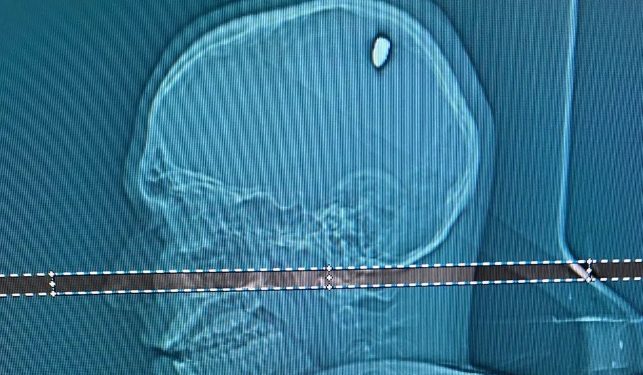

Após exames em um hospital particular de Juiz de Fora, foi identificada a bala, de calibre 9 milímetros, alojada na cabeça dele.

A cirurgia para retirada do projétil durou aproximadamente duas horas. Depois disso, ele permaneceu dois dias na CTI e mais um no quarto, até receber alta. Mateus agora se recupera em casa.